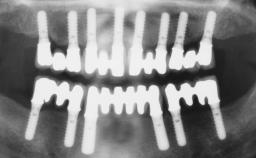

Conventional Loading of Eight Implants in the Maxilla and Final Restoration with a Full-Arch Gold-Ceramic FDP

| # of Implants | 8 |

| Type of Implants | One-Piece |

| SAC Level | Complex |

| Defining Characteristics | Fully edentulous upper jaw to be rehabilitated with four or more implants |